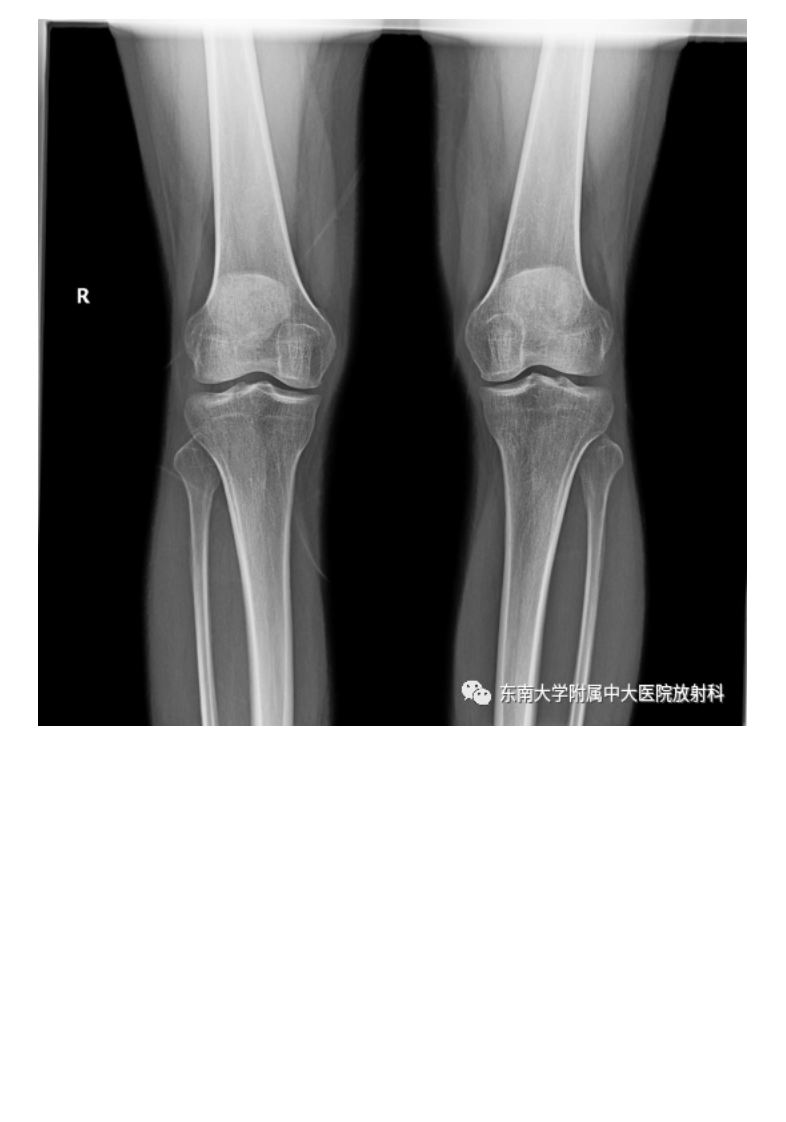

20210506_3【晨读结果公布】2021.05.06肌骨系统疾病——髌骨软化症.pdf